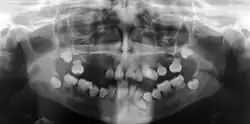

Dysplazja zębiny (ang. dentin dysplasia) – zaburzenie rozwoju zębiny. Wyróżnia się dwa typy schorzenia: typ I i typ II[2][3]. Dysplazja zębiny typu I polega na szczątkowym wykształceniu korzeni zębów. Na obraz kliniczny choroby składa się wczesna utrata uzębienia stałego i towarzyszący niedorozwój szczęk. Na radiogramie można stwierdzić skrócenie korzeni zębów i nieprawidłową morfologię tych części zębów, z obecnością punktowej zwiększonej przejrzystości lub torbieli. Kanały korzeni zwykle są nieobecne, komora miazgi jest częściowo lub całkowicie zamknięta. Kolor i morfologia uzębienia mlecznego i stałego są zazwyczaj prawidłowe, chociaż niekiedy zęby mogą być matowe, niebieskawe lub brązowawe. W typie II zęby mleczne są brązowawe lub niebieskawe, komora miazgi jest nieobecna; zęby stałe mają prawidłową morfologię (kształt i wielkość) i barwę lub są delikatnie przebarwione, w komorze miazgi mogą być obecne kamienie (ang. pulp stones)[4]. Leczenie polega na zastosowaniu implantów.